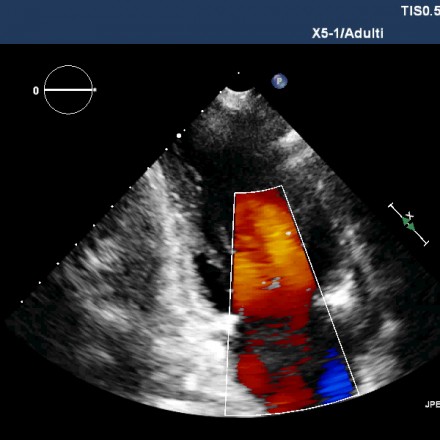

L’ECOCARDIOGRAFIA BIDIMENSIONALE, DOPPLER E COLOR DOPPLER è una metodica che sfruttando l’emissione di ultrasuoni e la cattura della rifrazione degli stessi che colpiscono il cuore, tramite apposite sonde, permette di visualizzare tutte le parti dell’organo e individuare eventuali patologie organiche e funzionali. http://essaynara.com/

Ecocolor doppler vascolare